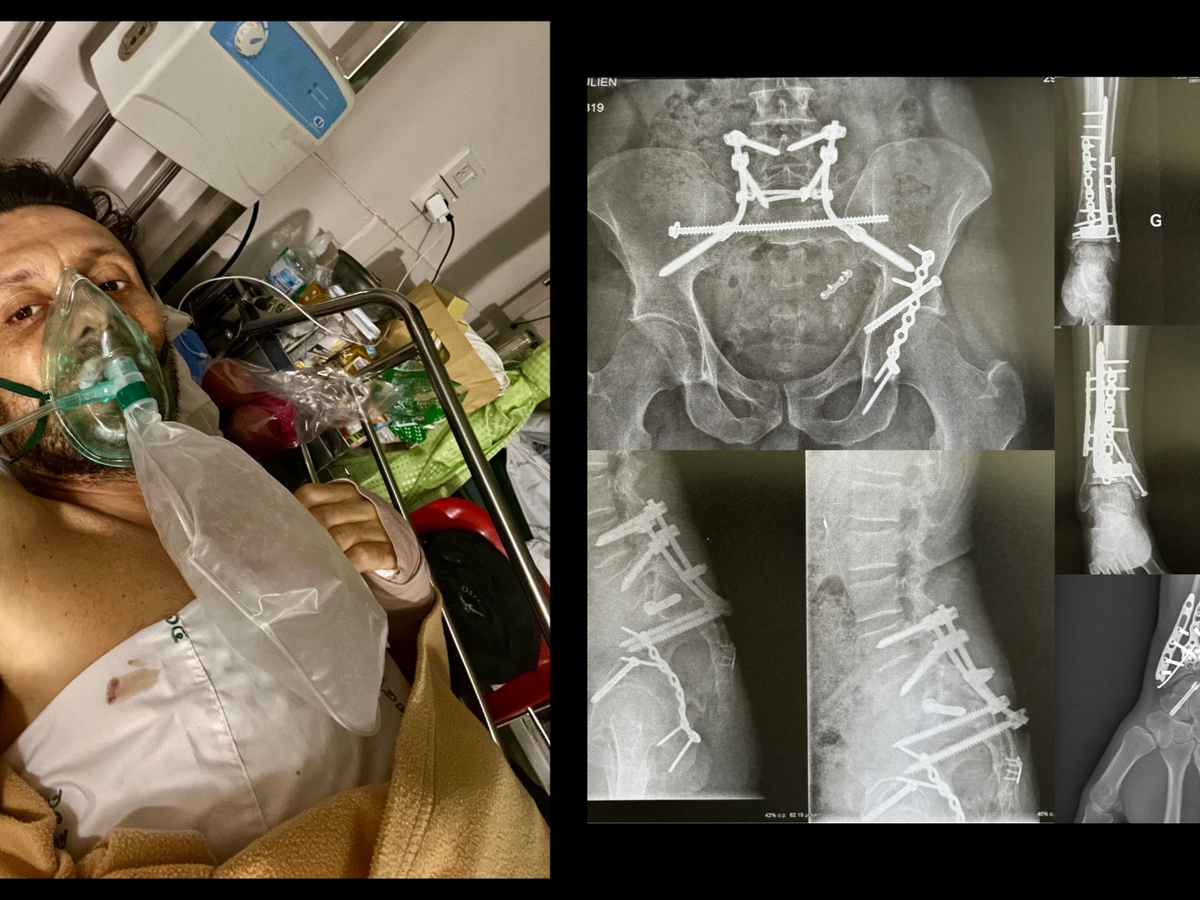

Two years ago, I fell 10 meters while traveling in Thailand, breaking 19 bones and nearly losing my life.

I survived six days in an abandoned hospice, two 23 hours-long surgeries, and 9 months in a wheelchair. I relearned how to move, sit, and walk — step by painful step.

The impact was devastating and I was found with multiple fractures — 19 in total: pelvis, sacrum, hip, both legs, wrist.

They rebuilt me with metal: rods, plates, screws — the only thing keeping me together.